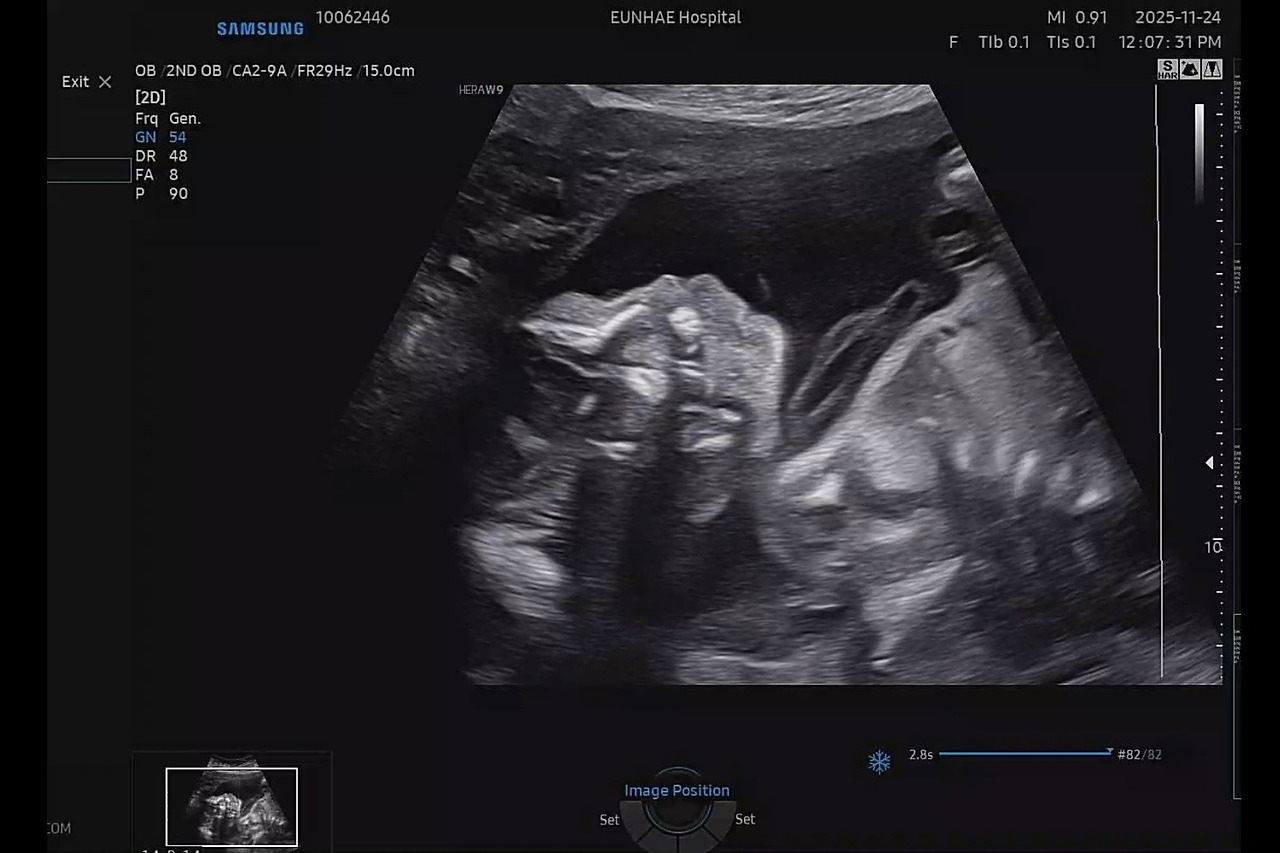

아내의 뱃속에 24주의 딸이 자라고 있습니다.

아내의 뱃속에는 24주를 막 지난 딸이 성장하고 있습니다. 아내와 함께 숙고해 ‘이수(李水)’로 이름도 지었습니다. 물처럼 유연하고 조화롭게 살아가길 바라는 마음을 담았습니다.